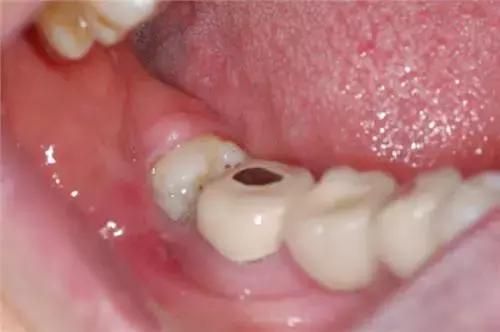

3.临床上智齿部分萌出,也是伴发智齿冠周炎的直接原因。智齿在萌生过程中,冠部往往被牙龈瓣覆盖,与牙冠之间形成较深的盲袋,食物及细菌极易嵌塞于盲袋内,一般很难通过漱口和刷牙被清理干净;加之口腔内有非常适宜的温度和湿度,致成为细菌繁殖的温床。

1、 由于萌出不全,后侧的牙龈覆盖,其部分牙冠形成冠周袋积存食物和细菌,可以造成局部软组织经常发炎,疼痛难忍,甚至导致张口受限而进食困难。

4、 会影响其他牙齿龋坏:阻生智齿能使第二磨牙龋坏。向前倾斜的智齿,其牙冠顶在前牙的颈部,这两颗牙之间形成一个滞留区,由于食物残渣的滞留,得不到正常清洁,细菌繁殖产酸,腐蚀牙齿,造成第二磨牙牙颈容易发生龋齿,往往就诊时已不能保留,需要拔除。